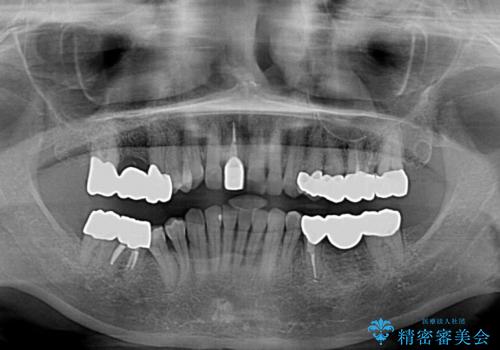

金属を全てセラミックに メタルフリー治療

- 口腔内にある銀歯を全て外したいとのことで来院された患者様です。

土台に含まれている金属も含め、口腔内の金属は全て除去し、抜歯しなければならない歯は抜歯し、オールセラミッククラウンやセラミックインレーにて治療することとしました。

上下奥歯の抜歯を同時期に行わず、下顎の治療を終えてから上顎を抜歯して治療を進めたため、1年ほどの期間を要しました。